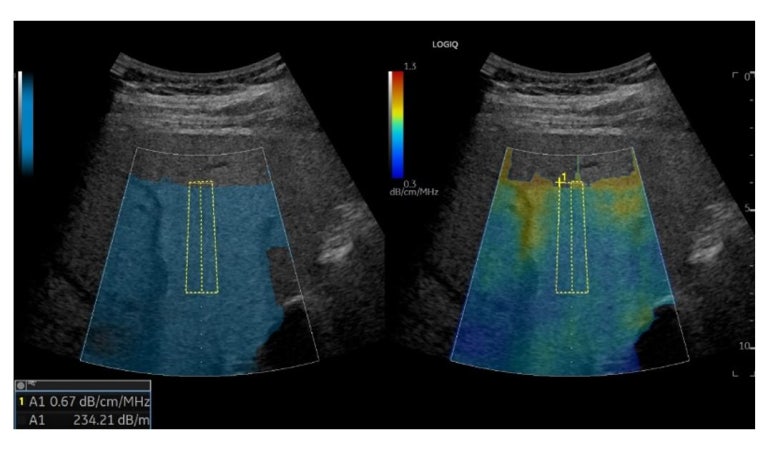

Ultrasound-Guided Attenuation Parameter, UGAP

UGAP(유갭)은 지방간을 분석하는 검사법입니다.

과거에는 비알콜성지방간질환/간염, 알콜성지방간염 환자에 대해 신장과의 에코도 차이, 횡격막 및 혈관벽의 구별정도를 가지고 정성적인 등급을 매겼습니다.

하지만 유갭 기능을 활용한다면 객관적인 숫자로 그 정도를 정량적으로 평가할 수 있습니다.

Hepatic assistant기능을 활용하면 간에 대한 SWE와 UGAP 연달아 시행할 수 있어 편리합니다.